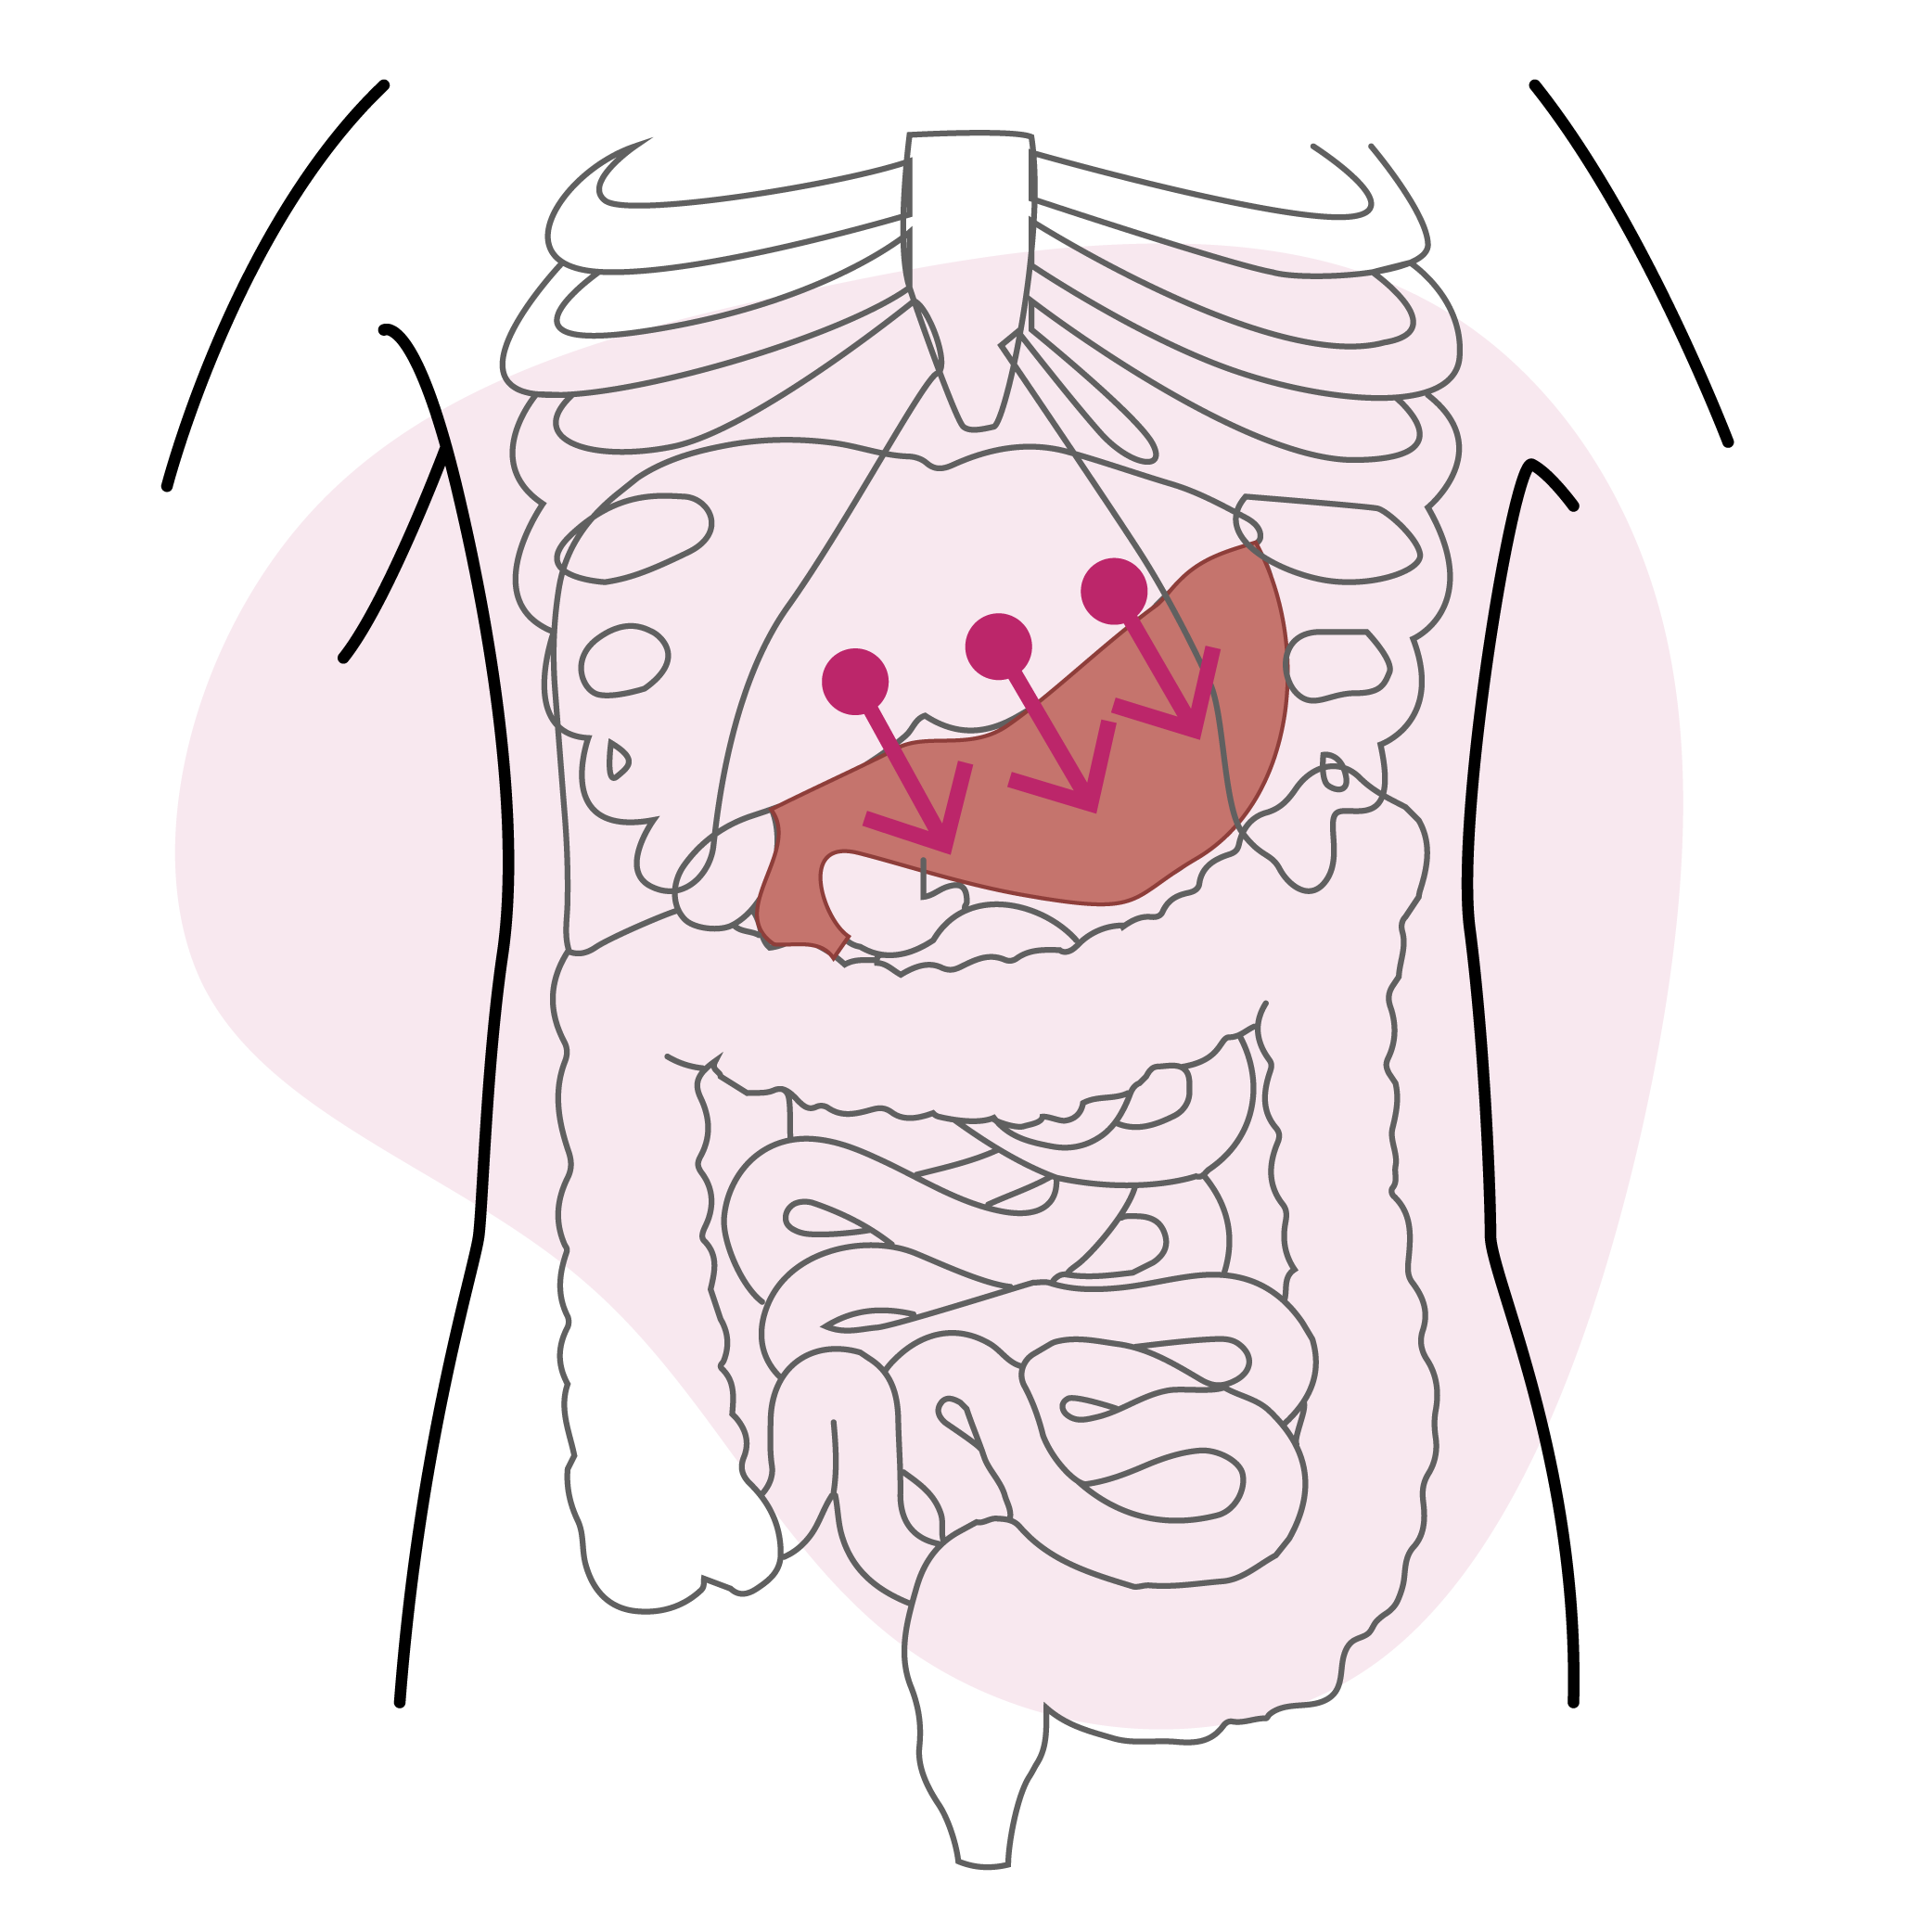

Libérer l’estomac

Libérer l’estomac